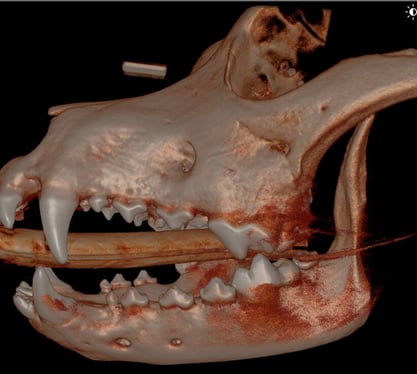

CT Imaging showed:

T/NV (non vital tooth) 204.

Missing 408 and 311, 411.

Beginning RR (root resorption) to lower rostral premolars - a common finding for dogs of this age and size

Below: 3D Overview before procedure: (left and right)

%20-%20March%202024/3D%20Overview%20(1).jpg?width=415&height=375&name=3D%20Overview%20(1).jpg)